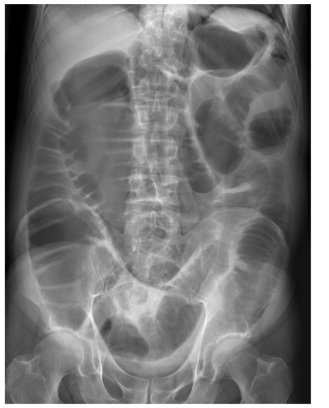

21

Q

24-year-old patient with suspected appendicitis. What does the image show?

Caecal volvulus

Normal appearances

Pneumoperitoneum

Small bowel obstruction

Toxic megacolon

A

Dilated loops of bowel with valvulae conniventes – lines crossing the full width of the bowel – indicates small bowel obstruction.

How well did you know this?